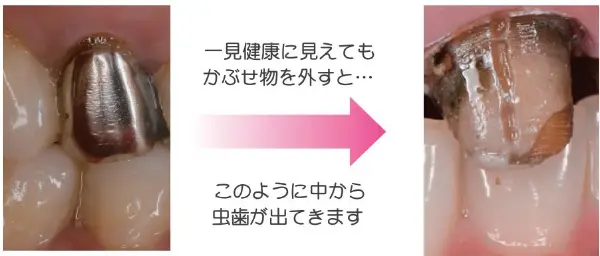

実は、銀歯・保険適用の詰め物は

歯とくっつかず再び虫歯へ…

一度治療をした歯が何故か再び虫歯になるのか、

疑問に思ったことはありませんか?

実は、金属と歯はくっつきません。

そのため従来の治療法では、

しっかり予防してもその隙間から細菌が侵入し、

10年後に2本に1本が再び虫歯になってしまうのです。